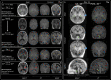

Findings: Between September 23, 2021 and October 25, 2022, 102 paired scans were acquired in 87 infants; 1.17 paired scans per infant. Median age 9 days, median postmenstrual age 40+2 weeks (range: 31+3-53+4). Infants had a range of intensive care requirements. No adverse events observed. Optimised ULF sequences can visualise key neuroanatomy and brain abnormalities. In finalised neonatal sequences: T2w imaging distinguished grey and white matter (7/7 infants), ventricles (7/7), pituitary tissue (5/7), corpus callosum (7/7) and optic nerves (7/7). Signal congruence was seen within the posterior limb of the internal capsule in 10/11 infants on finalised T1w scans. In addition, brain abnormalities visualised on ULF optimised sequences have similar MR signal patterns to 3T imaging, including injury secondary to infarction (6/6 infants on T2w scans), hypoxia-ischaemia (abnormal signal in basal ganglia, thalami and white matter 2/2 infants on T2w scans, cortical highlighting 1/1 infant on T1w scan), and congenital malformations: polymicrogyria 3/3, absent corpus callosum 2/2, and vermian hypoplasia 3/3 infants on T2w scans. Sequences are susceptible to motion corruption, noise, and ULF artefact. Non-identified pathologies were small or subtle.